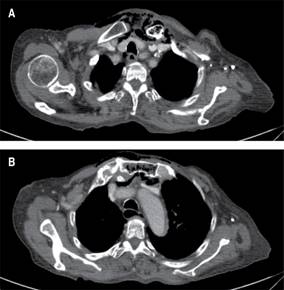

Durante el abordaje inicial en el servicio de urgencias, se decidió la colocación de sonda urinaria (la paciente aún tenía diuresis espontánea), con evidencia de piuria; se intentó colocar un acceso venoso central, palpando la presencia de enfisema subcutáneo, por lo que se solicitó realizar una tomografía computarizada; con reporte de un proceso inflamatorio localizado en la región cervical con extensión al mediastino superior, así como presencia de gas intramedular en clavícula izquierda y manubrio esternal, sugestivo de osteomielitis (Figuras 1 y 2). El estudio del líquido peritoneal obtenido a través del catéter de diálisis se encontró dentro de parámetros de referencia, por lo que ante la evidencia de choque séptico asociado a evidencia radiológica de mediastinitis Endo IIA, se propuso tratamiento quirúrgico urgente consistente en exploración y drenaje cervical, el cual no fue aceptado por los familiares de la paciente hasta 12 horas después del ingreso hospitalario. Se inició tratamiento antibiótico de amplio espectro (carbapenémico) desde el ingreso hospitalario y durante la cirugía se realizó un abordaje cervical en collar, 1 cm por encima de la escotadura esternal, se disecó por planos y se identificó presencia de líquido purulento proveniente de la articulación esternoclavicular izquierda; debido a la inestabilidad hemodinámica de la paciente, manifestada por hipotensión persistente, uso de aminas presoras con dosis progresivas y presencia de extrasístoles ventriculares, se decidió limitar la cirugía a control temporal del foco infeccioso con drenaje, irrigación y debridación parcial del área afectada.

Figura 2: A) Neumomediastino con destrucción ósea y aire en borde esternal de clavícula izquierda. B) Neumomediastino con destrucción ósea y aire en manubrio esternal.